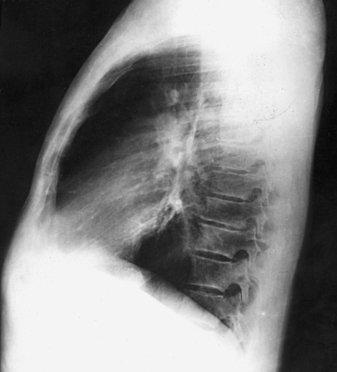

Structures shown: The preliminary left lateral chest position is used to show the heart, the aorta, and left-sided pulmonary lesions (Figs. 10-37 and 10-38). The right lateral chest position is used to show right-sided pulmonary lesions (Fig. 10-39). These lateral projections are employed extensively to show the interlobar fissures, to differentiate the lobes, and to localize pulmonary lesions.

Fig. 10-38 A, Left lateral chest. B, Right lateral chest on same patient as in A. Note the size of the heart shadows.